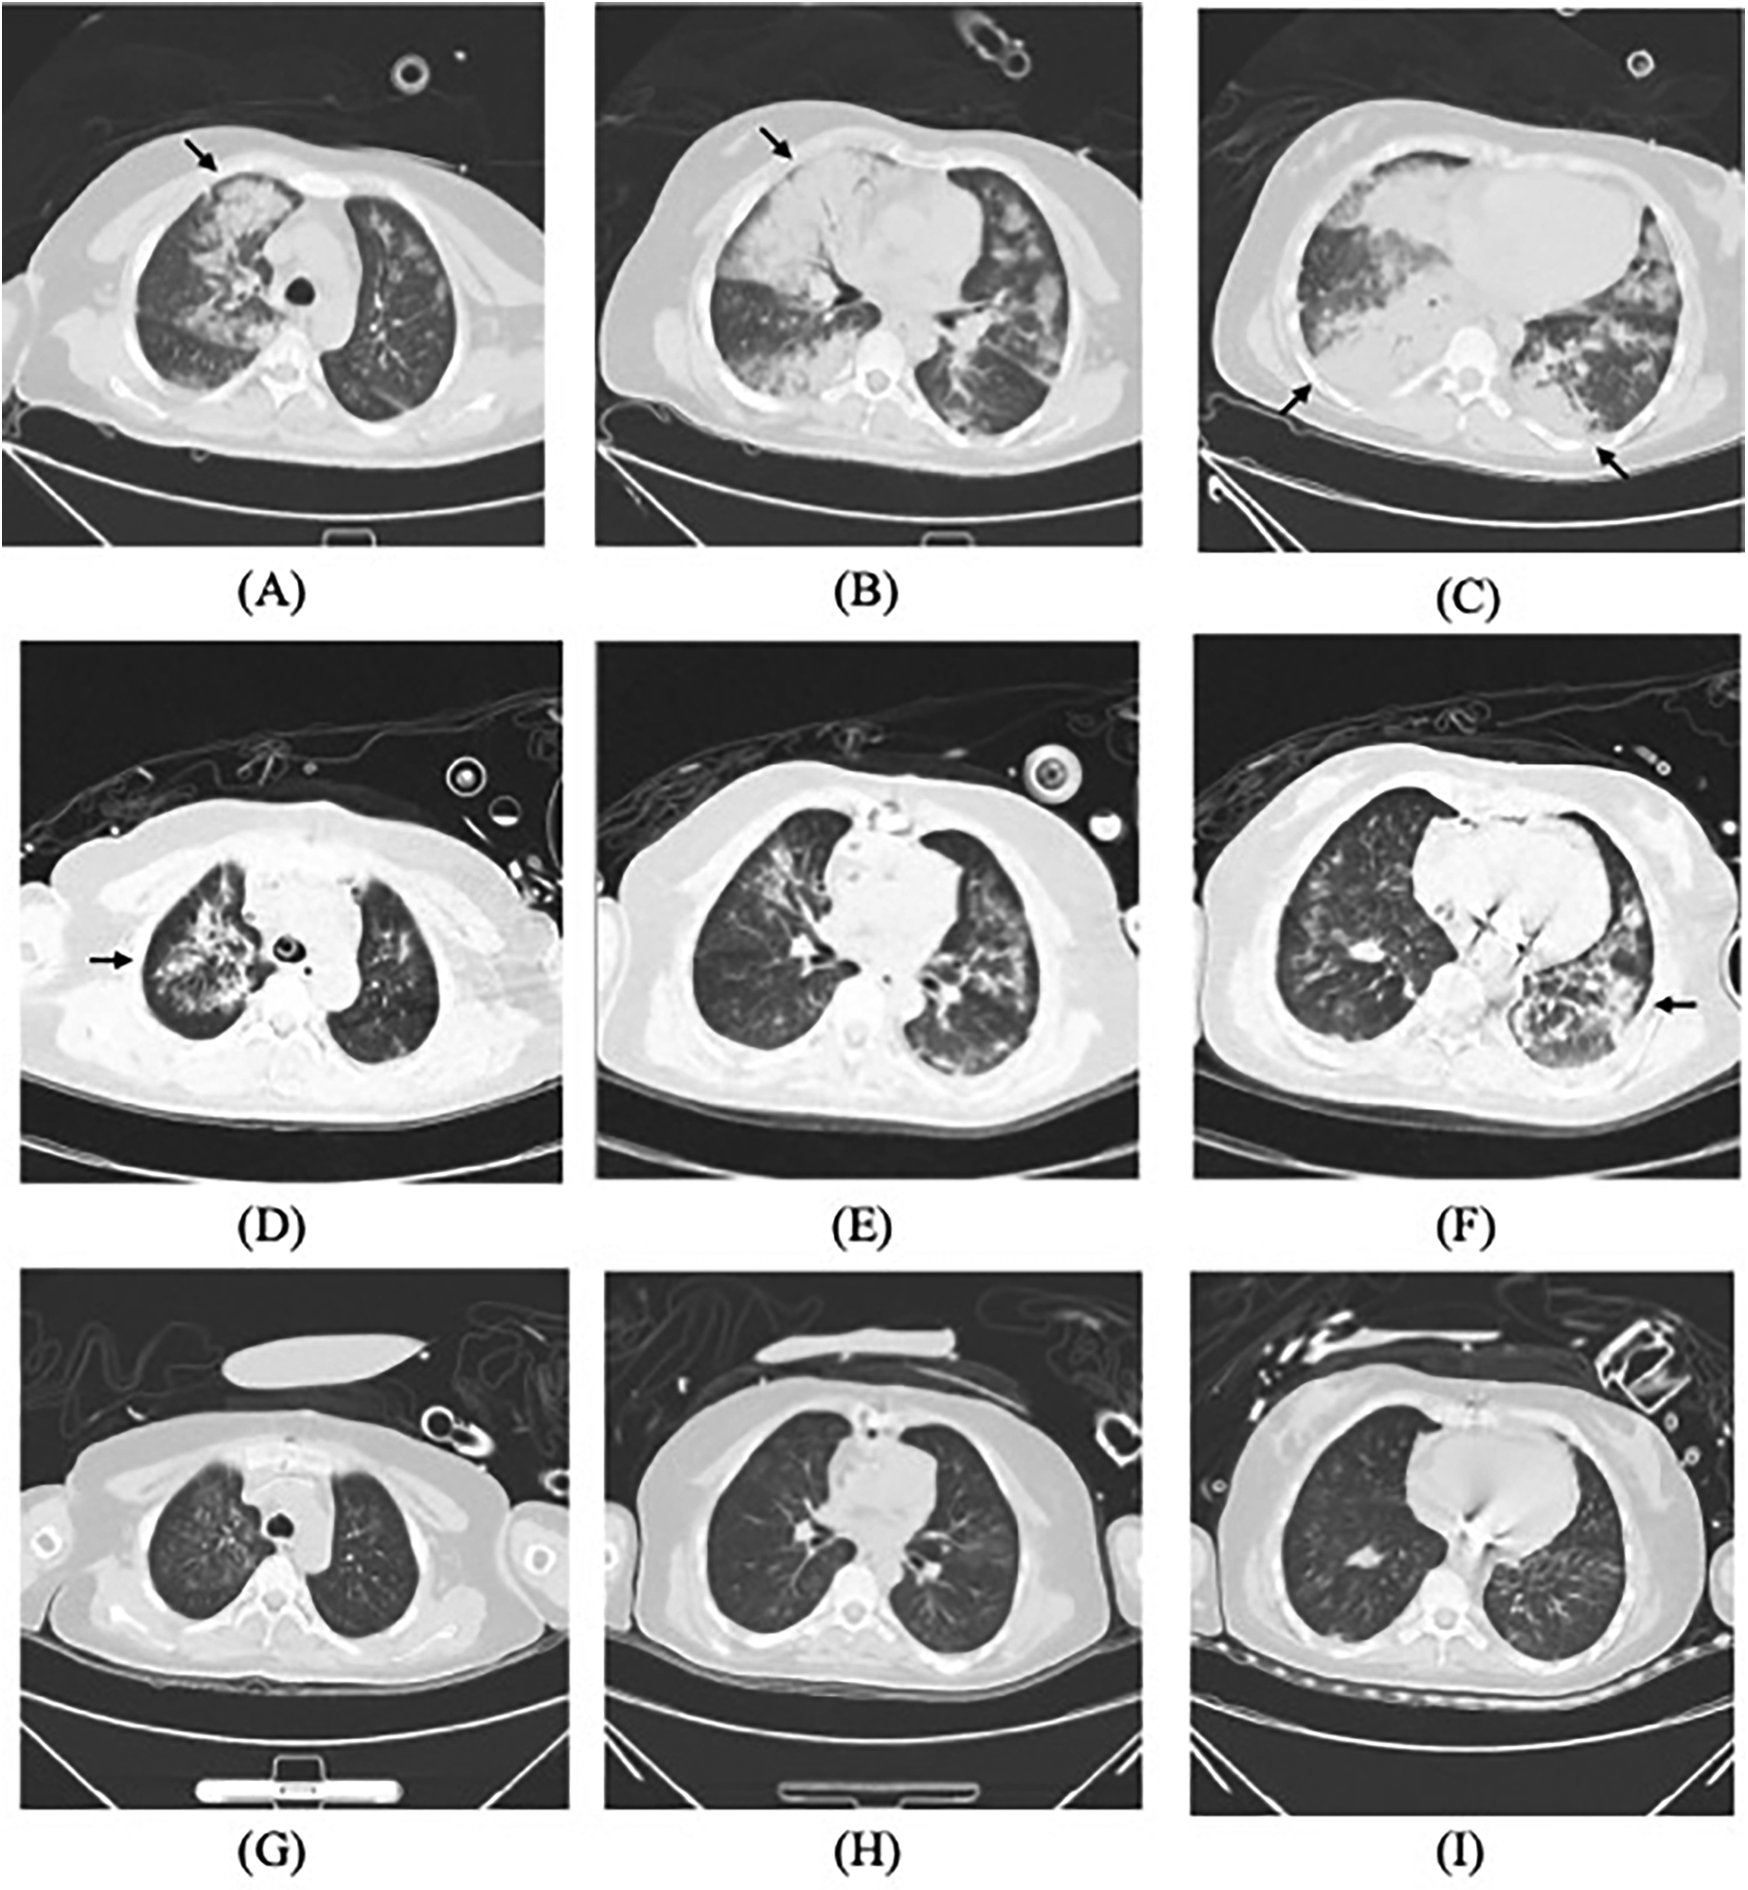

Figure 1

Lung CT scans: (A–C) on admission, (D–F) on the postoperative day 3, and (G–I) almost one week after initiating targeted treatment, demonstrating gradual resolution of pulmonary infiltrates (arrows).

On admission, she exhibited signs of acute left heart failure. Physical examination documented a temperature of 36.3°C, tachycardia (145 bpm), hypotension (92/52 mmHg), tachypnea (28 breaths/min) with oxygen saturation 88% on room air. Widespread bilateral pulmonary crackles and an apical gallop rhythm with a grade III/VI holosystolic murmur at the mitral area were noted. Blood tests revealed elevated levels of C-reactive protein (37.5 mg/L, normal < 3 mg/L) and N-terminal B-type natriuretic peptide (12,855 pg/mL, normal < 125 pg/mL), while white blood cells (WBC) (8.12 × 109/L), platelet (257 × 109/L), hemoglobin level (143 g/L), erythrocyte sedimentation rate (16 mm/h), and hepatic and renal function were all normal. Chest computed tomography (CT) showed extensive bilateral pulmonary infiltrates with significant consolidation (Figures 1A–C). The electrocardiogram indicated supraventricular tachycardia at 164 bpm with 1 mm ST segment depression in leads V1 to V6. Transthoracic echocardiography revealed mitral valve papillary muscle rupture and a suspicious mass-like lesion protruding into the left atrium (Figures 2A,B). Emergent coronary computed tomography angiography demonstrated chronic occlusion of the left anterior descending artery, with retrograde perfusion supplied by collateral vessels originating from the circumflex artery, effectively excluding acute coronary syndrome.

Postoperatively, the patient maintained hemodynamic stability on ECMO support without vasoactive drugs. Intraoperative absence of valvular vegetations combined with negative extensive microbiological investigations (including blood cultures, serological assays, and valve tissue smear/cultures) preliminarily excluded IE. Consequently, antimicrobial therapy was de-escalated to cefuroxime. However, on postoperative day (POD) 3, the patient developed septic shock, necessitating reinitiation of NE infusion (0.3–0.4 µg/kg/min). Her clinical manifestations included fever (39°C), leukocytosis (WBC increased from 8.75 to 19.47 × 109/L), and markedly elevated inflammatory biomarkers: procalcitonin rising from 0.46 to 21 ng/mL (normal < 0.05 ng/mL) and IL-6 > 1,000 pg/mL (normal < 5.9 pg/mL). Follow-up chest CT revealed asymmetrical peribronchial infiltrates with progression in the right upper lobe compared to preoperative imaging (Figures 1D–F), These radiographic patterns were inconsistent with cardiogenic pulmonary edema. Given the atypical disease progression and strong suspicion for occult infection, a comprehensive microbiological reevaluation was undertaken, including repeat blood and tracheal aspirate (TA) cultures, and metagenomics next generation sequencing (mNGS) of paired blood and bronchoalveolar lavage fluid (BALF) specimens. Notably, BALF mNGS detected T. whipplei as the dominant pathogen (266,358 sequence reads and 99.7% relative abundance), whereas blood mNGS, blood culture and TA culture remained consistently negative. These findings strongly suggested WD with pulmonary involvement. Subsequent histopathological reassessment of valve tissue definitively confirmed TWE based on characteristic features displayed by special staining techniques, including Hematoxylin and Eosin showing foamy macrophage infiltration, CD68 immunohistochemistry confirming histiocytic lineage, and periodic acid-Schiff (PAS) highlighting intracellular bacilli (Figures 3A–C). Antimicrobial therapy was escalated to meropenem (1 g IV q8 h) plus oral doxycycline (100 mg twice daily). Following 5 days of targeted antimicrobial therapy, chest CT showed significant resolution of pulmonary infiltrates (Figures 1G–I), with resolution of septic shock permitting ECMO discontinuation on POD 9. One week later, meropenem was switched to ceftriaxone (2 g IV qd) following normalization of temperature and WBC. The patient was successfully extubated on POD 12 and discharged from the ICU on POD 16. Upon targeted history-taking, she specifically denied classical WD symptoms, such as diarrhea, abdominal pain, weight loss, or arthralgias. She was discharge on POD 22 with continuation therapy comprising doxycycline and co-trimoxazole (Figure 4). At 3-month follow-up, the patient was in good condition. Given her persistent immunocompromised status, indefinite co-trimoxazole suppression therapy was recommended.